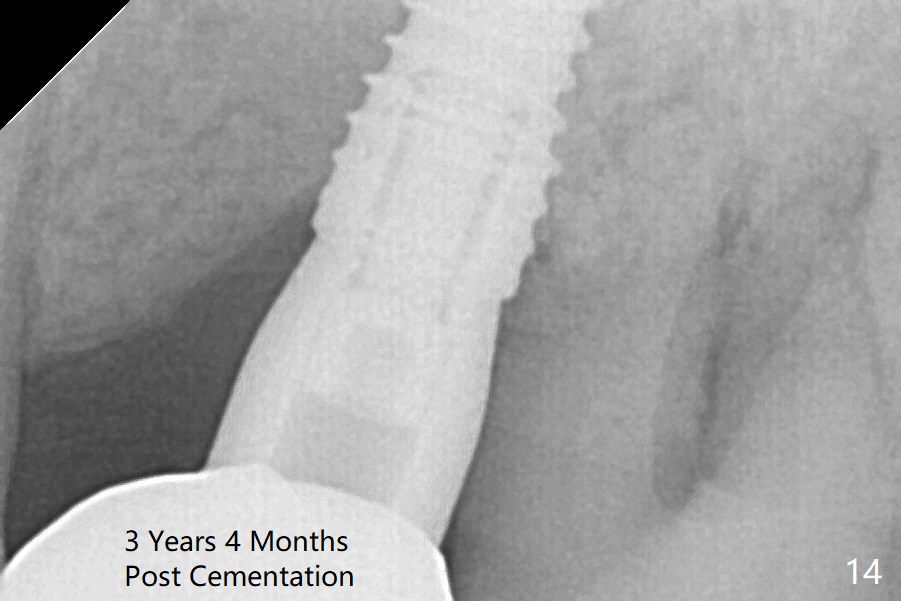

While there is minimal bone loss at #13 and 15 three years and 4 months post cementation, the tooth #14 and 18 are mobile (Fig.13,14).